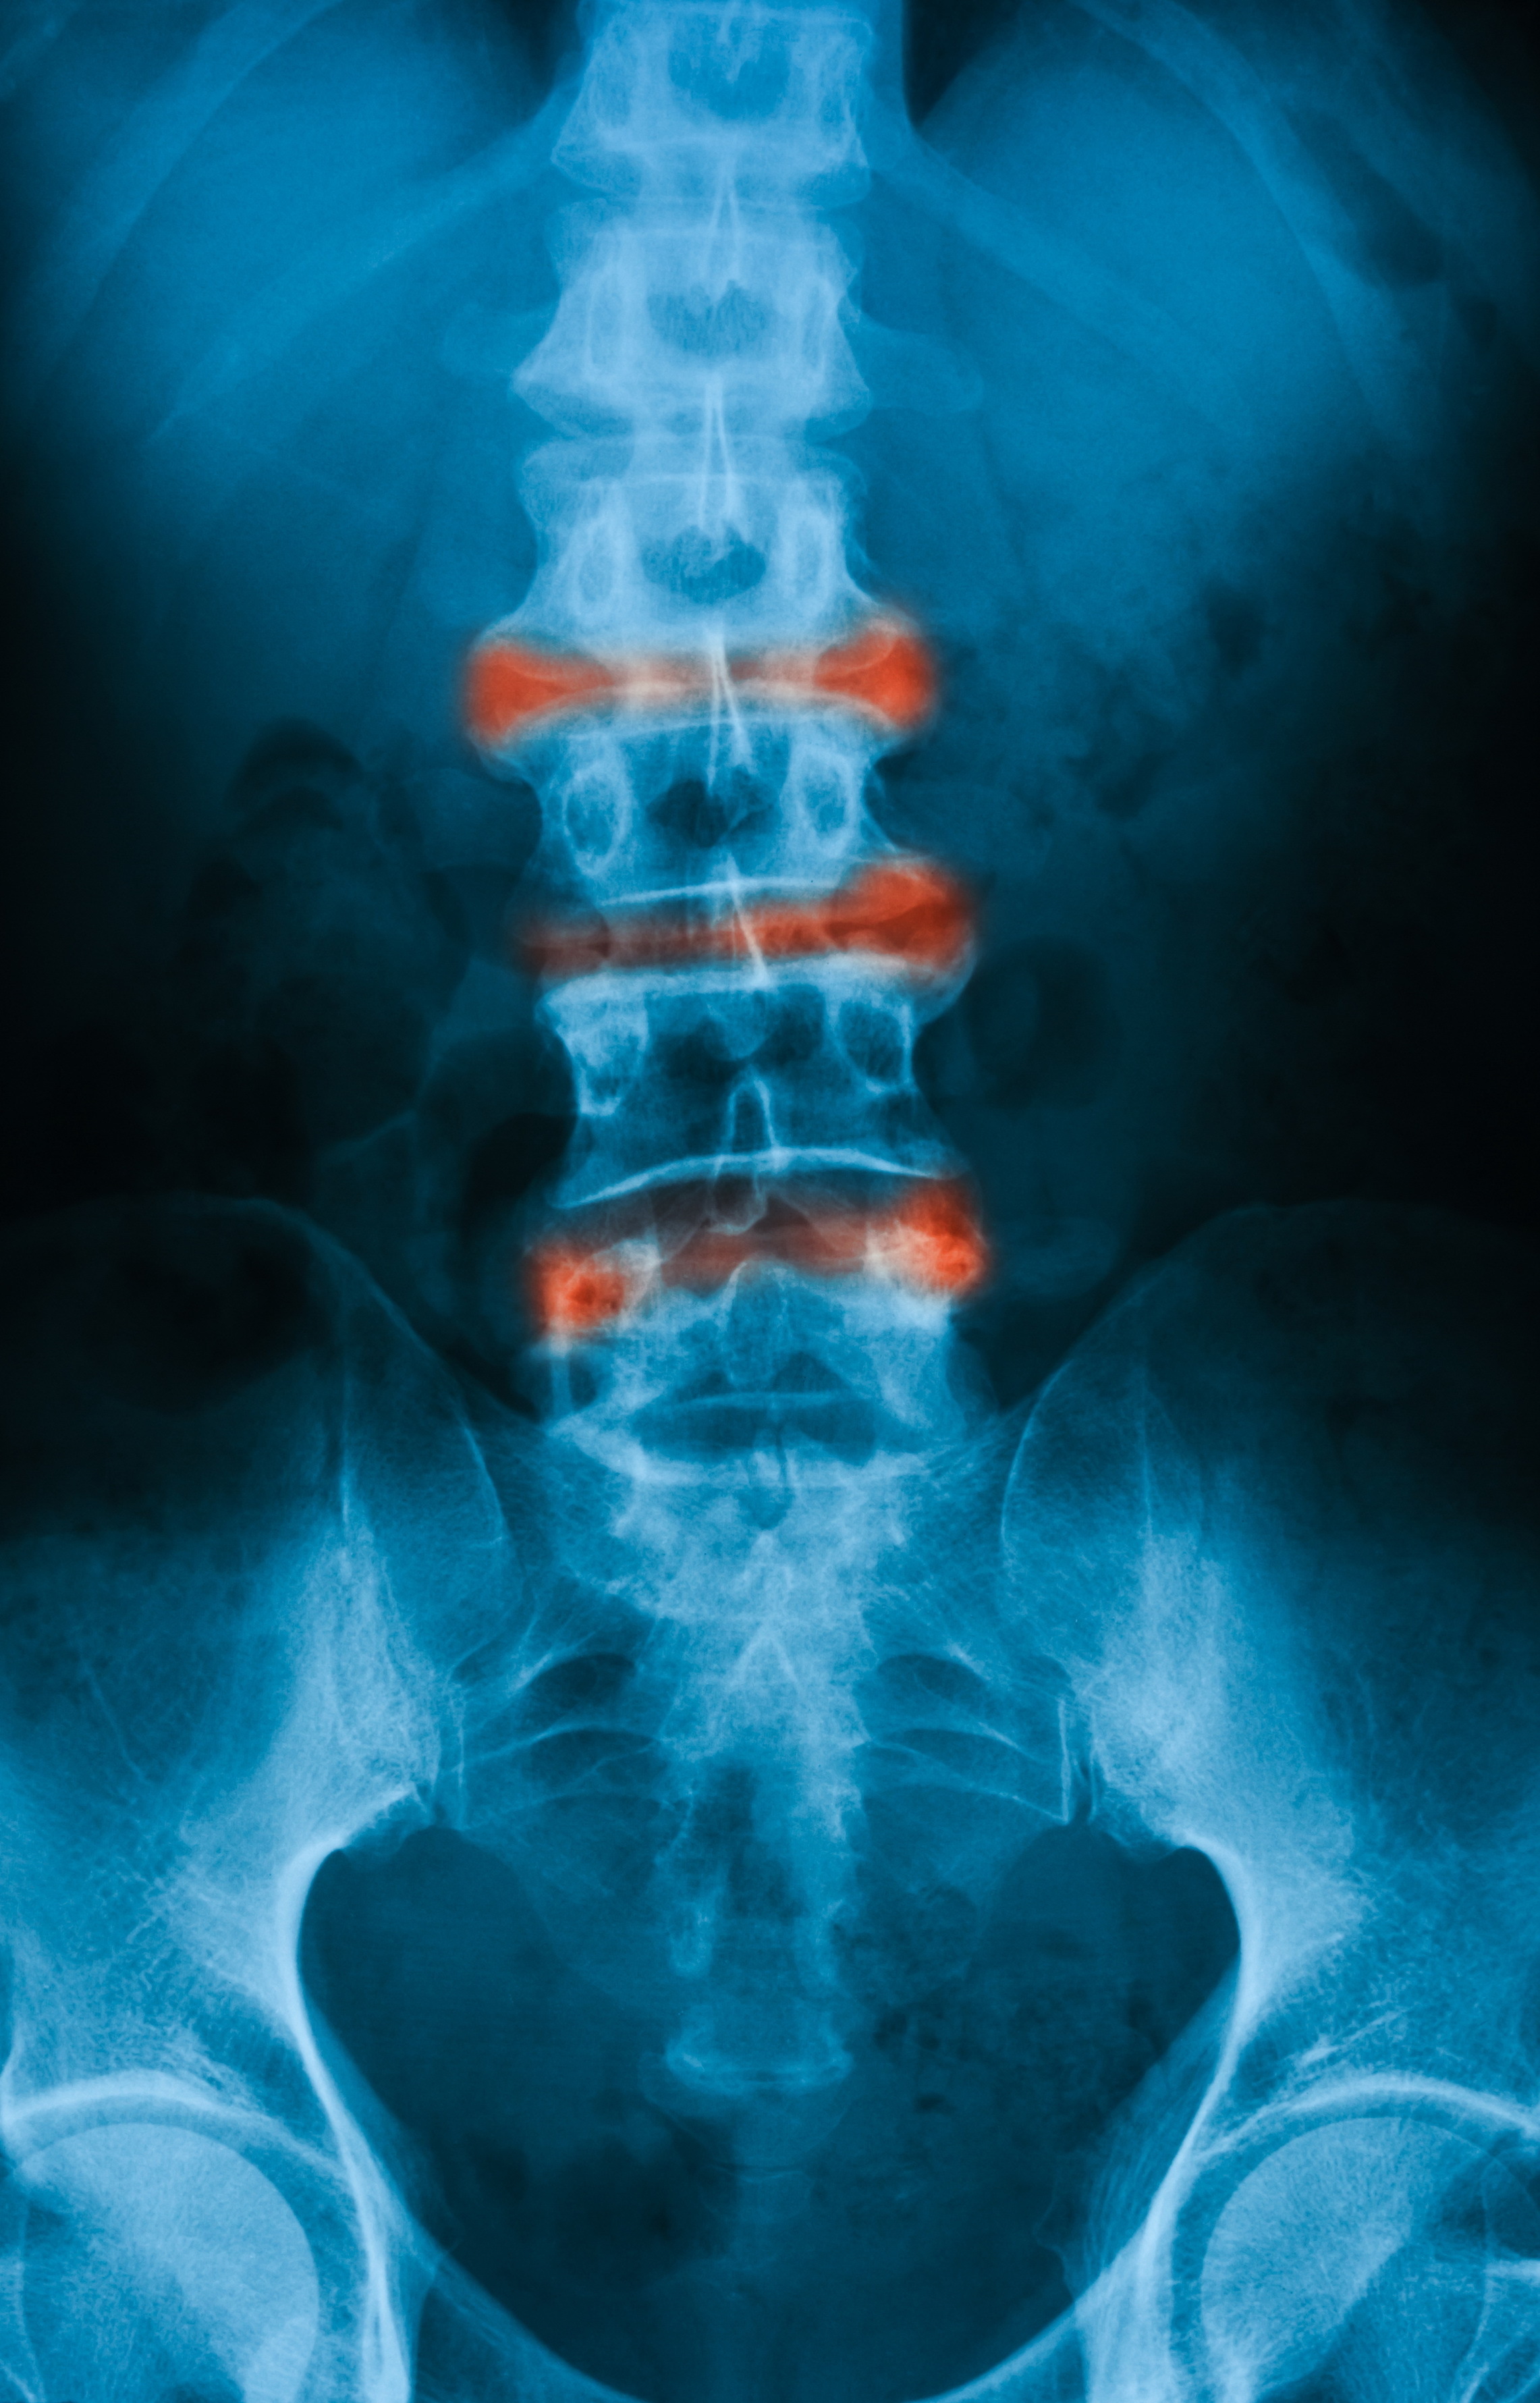

Η δισκογραφία είναι μια επεμβατική διαγνωστική εξέταση που βοηθά τον κλινικό ιατρό να εξετάσει τους μεσοσπονδύλιους δίσκους της σπονδυλικής σας στήλης και να εντοπίσει ποιοι από αυτούς είναι υπεύθυνοι για τον πόνο του ασθενούς. Τα αποτελέσματα μιας δισκογραφίας μπορούν να επιβεβαιώσουν την ανάγκη για χειρουργική επέμβαση, καθώς καταδεικνύουν το αίτιο του πόνου, βάσει των αλλοιώσεων που παρατηρούνται στους δίσκους μετά από έγχυση σκιαγραφικής ουσίας για την απεικόνιση αυτών. Η τεχνική διενεργείται όταν τίθεται διαφοροδιαγνωστικό πρόβλημα, όσον αφορά περιπτώσεις ασθενών όπου η κλινική σημειολογία και συμπτωματολογία δεν είναι σαφής ως προς το γενεσιουργό αίτιο του άλγους.

Με τον ασθενή σε πρηνή θέση, υπό τοπική αναισθησία ή μέθη και κάτω από συνεχή ακτινοσκοπική καθοδήγηση, εισάγεται μια ειδική βελόνα σε έναν ή περισσότερους δίσκους στην οσφύ. Στη συνέχεια, γίνεται έγχυση μικρής ποσότητα σκιαγραφικής ουσίας σε κάθε δίσκο για την απεικόνιση αυτού.. Η σκιαγραφική ουσία θα αυξήσει την ενδοδισκική πίεση, γεγονός που μπορεί να εκλύσει πόνο, ο οποίος είναι ενδεικτικός του πάσχοντα δίσκου. Η ακτινοσκοπική απεικόνιση των δίσκων θα βοηθήσει να εξαχθούν τα απαιτούμενα συμπεράσματα και να εντοπισθεί η πηγή του πόνου. Όταν η έγχυση γίνεται σε έναν φυσιολογικό δίσκο, ο ασθενής νιώθει μια ελαφρά πίεση. Όταν, αντίθετα, εισέρχεται σκιαγραφική ουσία σε μη φυσιολογικό δίσκο, ο ασθενής νιώθει έντονο πόνο.